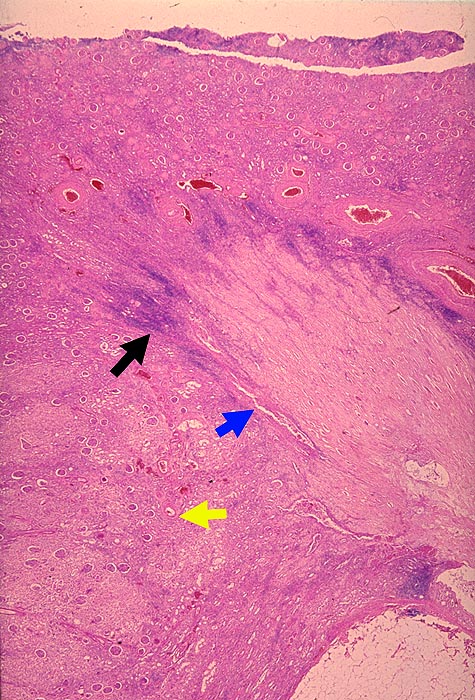

AP/ Analgetikanephropathie

Analgetikanephropathie

Niere

Morphologie

Pathologischer Befund